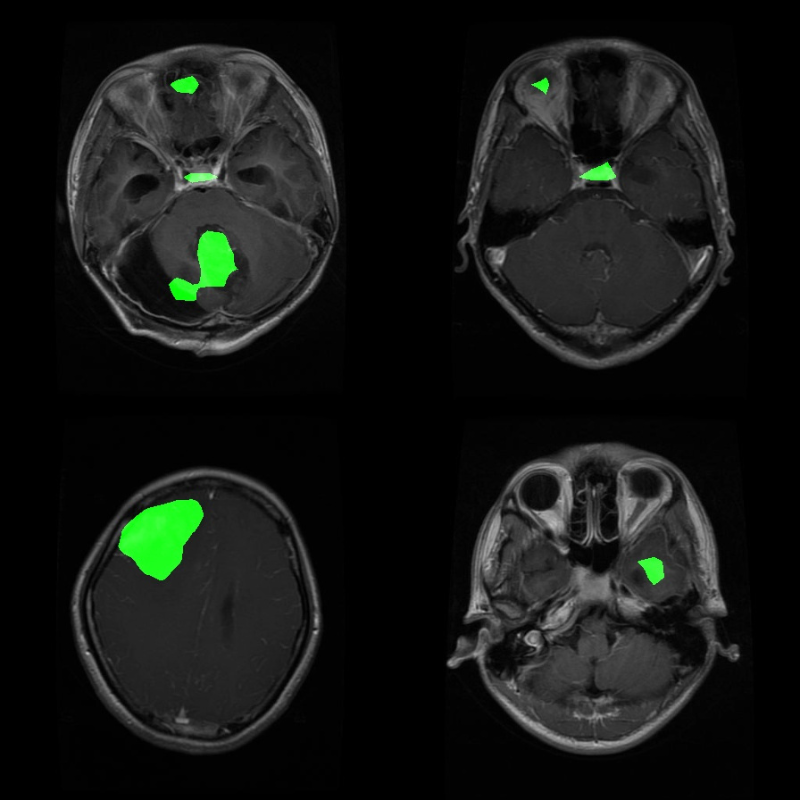

First, let’s analyze some results where the model seems to be performing well. The segmented region in green is the model inference, and white is the ground truth.

The above are a few instances where the model seems to be performing somewhat well.